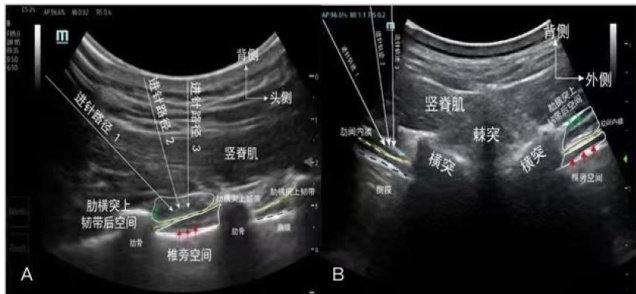

横突间阻滞(Intertransverse process block,ITPB)是为提高安全性和降低操作难度提出的一种类椎旁神经阻滞技术,阻滞目标区域位于肋横突上韧带的后方空间。(剩余10668字)